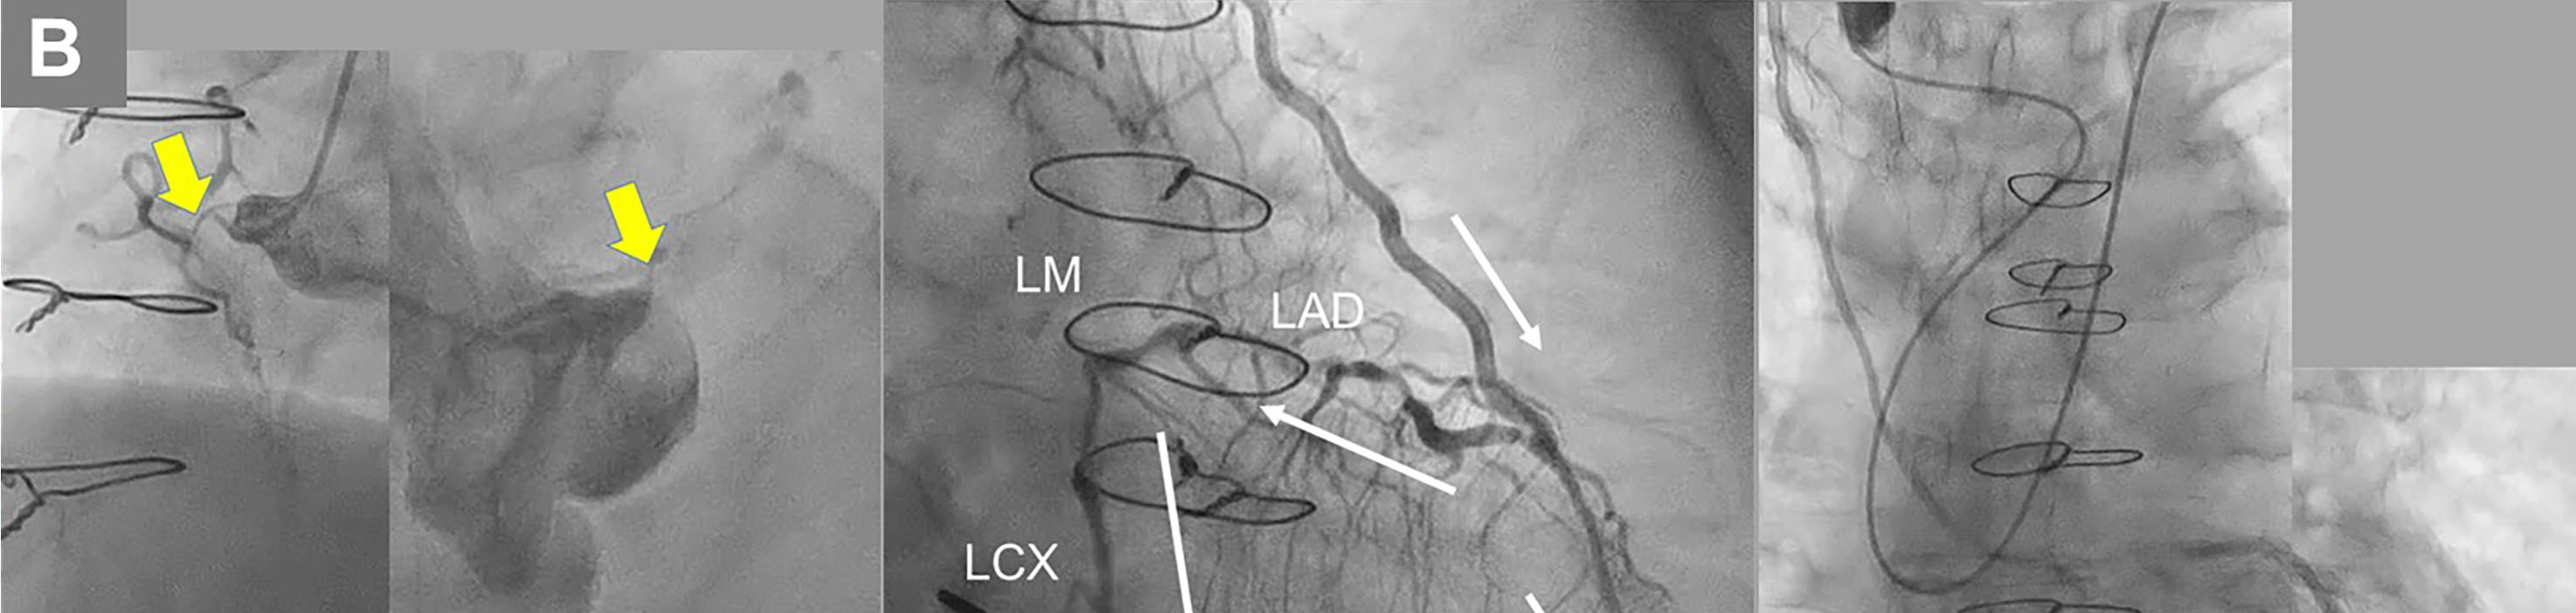

An 83-year-old man who had undergone coronary aorta bypass graft surgery 25 years ago required treatment for new-onset worsening angina. Coronary computed tomography angiography (CCTA) showed total occlusion of the left main coronary artery (LM), proximal obtuse marginal (OM) branch and proximal right coronary artery (RCA), a tight, calcified lesion in the proximal left anterior descending artery (LAD) (Figure A), patent bypasses of the left internal thoracic artery (LITA) to the LAD and the right internal thoracic artery (RITA) to the OM branch, and occlusion of the saphenous vein graft (SVG) from the aorta to the right coronary artery (RCA). Coronary angiography revealed total occlusion of the RCA and LM in their ostia (Figure B-a, b), retrograde perfusion to the proximal LAD and left circumflex artery (LCX), distal RCA by LITA-LAD graft (Figure B-c; Video 1), and limited perfusion of the OM branch by the RITA-OM branch graft (Figure B-d; Video 2). The symptom derived from a large myocardial ischemia in the postero-lateral and inferior areas.

Since CCTA indicated a blunt-type LM chronic total occlusion (CTO) in the straight route that was composed of fibrous tissue and connected to distal bifurcation (Figure A), percutaneous coronary intervention (PCI) for LM-CTO was performed with contralateral injection from the LITA-LAD. A 7-French AL2.0 SH guide catheter (Heartrail II, Terumo) was engaged in the LM and a tapered stiff guidewire (X-treme XTA, Asahi Intec) penetrated the CTO lesion and crossed to the LCX (Video 3). Intravascular ultrasound confirmed the guidewire’s penetration of the true lumen. (Figure C; Video 4). A 3.5 x 22-mm zotarolimus-eluting stent (Resolute Onyx, Medtronic) was implanted from the LM ostium to the proximal LCX (Figure D-a). Proximal optimization with a 4.0-mm balloon (Figure D-b), and final kissing balloon inflation with 3.5 and 2.5-mm balloons (Figure D-c) followed. Complete antegrade flow from the LM to LCX and good collateral flow into the distal RCA was achieved (Figure E-a, b; Videos 5 and 6). The proximal to middle LAD lesions were left untouched due to sufficient flow from the LITA-LAD graft (Figure E-c). Informed consent was obtained from the patient prior to all procedures.